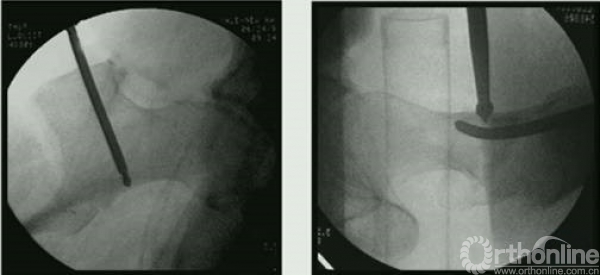

或采用钳加复位,复位之后可以较好的植入头钉。

牵引钳加复位后。

微创钳加复位。